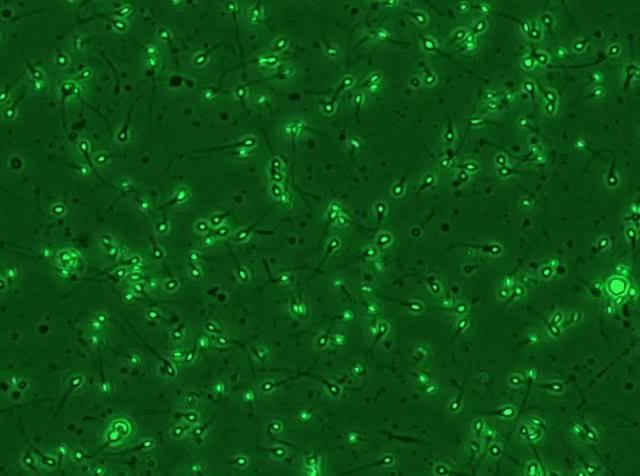

有些人的精子,“精力旺盛”↓

有些人的精子,“不动如山”↓

不要慌!我们先要了解一个基本概念: “精子存活率” ——即在所有计数精子中活精子的比例,主要目的是检测精子的死与活。

活动的精子肯定是活的,就不多说了。但对于那些 不活动的精子,是不是都死了呢?

害,那只能说——这些精子大多都是 “演技派” 。

真正判断精子是生是死,不能光看它动还是不动。

一般实验室里观察到的 不动精子,实际有两种情况:

“我死了”

确实阵亡了,所以他们动弹不得,但这只能是不动精子中的一部分。

“我装的”

活着,但处于静止状态 (装死),可谓是真正的“戏精”。

或是尾部有缺陷,导致活动受限,又或是能量提供不足等其他原因造成不动的状态。

他们虽然活着,却总是给人一种死掉的错觉。

总而言之,实验室会 运用存活率 这个参数,来看看这些“戏精”的比例,从而 判断精子质量。

尤其是前向运动精子小于40%的精液标本,存活率就非常重要,有助于死精子症和不动精子症的鉴别,进而指导临床治疗和辅助生殖。